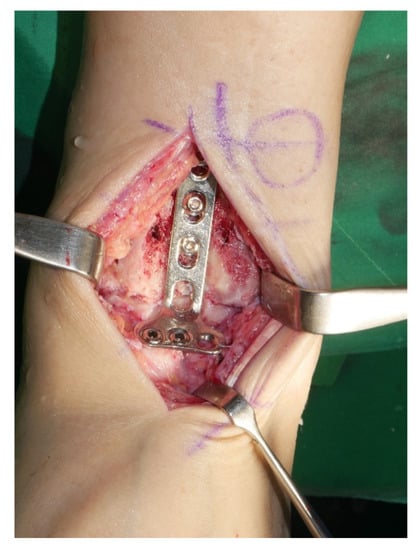

Surgery was performed with the patient in the lateral decubitus position, and it was possible to change to the supine position during the anterior approach. All patients received prophylactic antibiotics before surgery. An 8 to 10 cm lateral incision was made along the posterior border of the lateral malleolus to obtain a sufficient distance from the anterior incision (Figure 2). Soft tissue dissection was performed between the periosteum and the distal fibula to preserve the blood supply of the soft tissue. After exposure of the distal fibula, the fibula was transected 4 to 5 cm proximal to the ankle joint (Figure 3). The cartilage and subchondral bone of the tibiotalar joint were removed using curettes, osteotomes, and burrs through the lateral ankle joint (Figure 4). Following joint preparation, an anterior longitudinal incision of 6 to 8 cm was made by keeping a distance of 7 cm from the lateral incision. After dissection was performed between the tibialis anterior and extensor hallucis longus tendons to expose the joint, cartilage and subchondral bone of the medial gutter were removed (Figure 5). While the tibiotalar joint was being prepared, the resected fibular fragment was hemisected in the sagittal plane for use as a bone graft (Figure 6). The medial half was used as the filler of the arthrodesis site, and the lateral half was used as a lateral strut. The tibiotalar joint was reduced in a neutral and plantigrade position and temporarily fixed using a 2.4 mm-Steinmann pin. Subsequently, the arthrodesis site was fixed using the first 6.5-mm partially threaded cannulated screw from the posterior malleolus along the longitudinal axis of the talar neck and into the talar head as a homerun screw. The second 6.5-mm cannulated screw was placed from the metaphyseal flare of the medial distal tibia into the medial talar body. After screw fixation, additional anterior plating was performed using a 3.5-mm T-plate (Synthes, Paoli, PA, USA) in 29 ankles and an anatomical anterior fusion plate (Arthrex Inc., Naples, FL, USA) in 7 ankles through anterior incision (Figure 7). The lateral half of the resected fibula was fixed by four cancellous screws in its original anatomical position as a natural lateral bony plate (Figure 8). Reduction state and screw positioning without penetration of the subtalar joints were confirmed via fluoroscopy (Figure 9). The extensor retinaculum was meticulously closed with 2-0 absorbable sutures, followed by subcutaneous closure with 3-0 absorbable suture. The skin was closed with 4-0 monofilament sutures using the modified Allgöwer–Donati technique. Short leg casts were applied for 4 weeks following surgery. At 2 weeks after surgery, partial weight-bearing was started with crutches. Full weight-bearing with and without an ankle orthosis was allowed at 4 weeks and 8 weeks after surgery, respectively.

Figure 7. After screw fixation, additional anterior plating was performed through anterior incision.